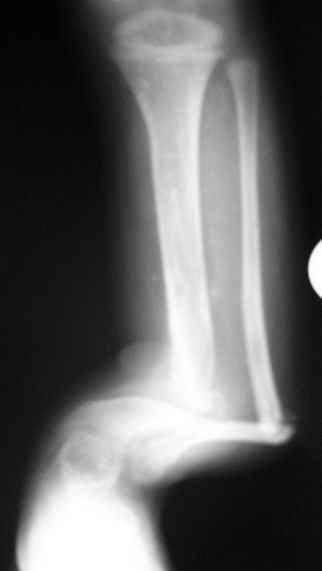

Уважаемые коллеги,Госпитализировали ребенка 4 лет с врожденной деформацией голени.

Нога опороспособна, безболезненна, выраженная хромота за счет укорочения.Признателен за рекомендации и высказанные мнения.Евгений И Чекашкин

диспластического типа с полной окклюзией к.м. канала.